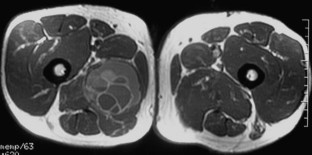

We describe the clinical, histological and radiological features of an unusual magnetic resonance imaging (MRI) and deep intramuscular location of GCT–ST with fluid-fluid levels (FFLs) simulating other soft tissue tumors or a hydatid cyst in a 52-year-old man. The lesion was resected.

Neither metastasis nor recurrence has occurred in the 6-month period since resection. A review of the literature did not reveal any similar description of intramuscular GCT-ST.

GCT-ST should be included in the differential diagnosis of soft tissue tumors with FFLs.